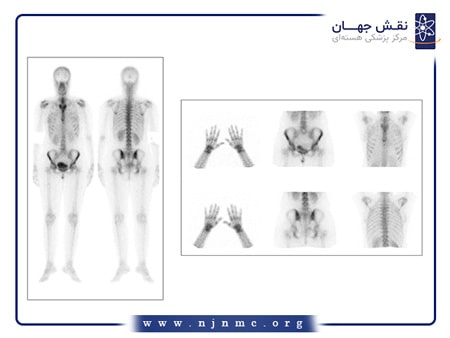

اسکن هسته ای استخوان

اسکن هستهای استخوان یک نوع تصویربرداری با مواد رادیواکتیو ضعیف میباشد که به تشخیص انواع مشکلات و بیماریهای مختلف استخوانی از جمله سرطان، عفونتها، بیماریهای التهابی، دردهای استخوانی نامشخص و شکستگیها کمک میکند. همچنین برای بررسی پاسخدهی درمان در بیماران سرطانی میتوان از این اسکن بهره گرفت. در این روش تصویربرداری ماده رادیواکتیو تزریق شده در استخوانها تجمع مییابد و پس از گذشت چند ساعت با استفاده از دستگاه گاما کمرا تصاویر گرفته میشوند.